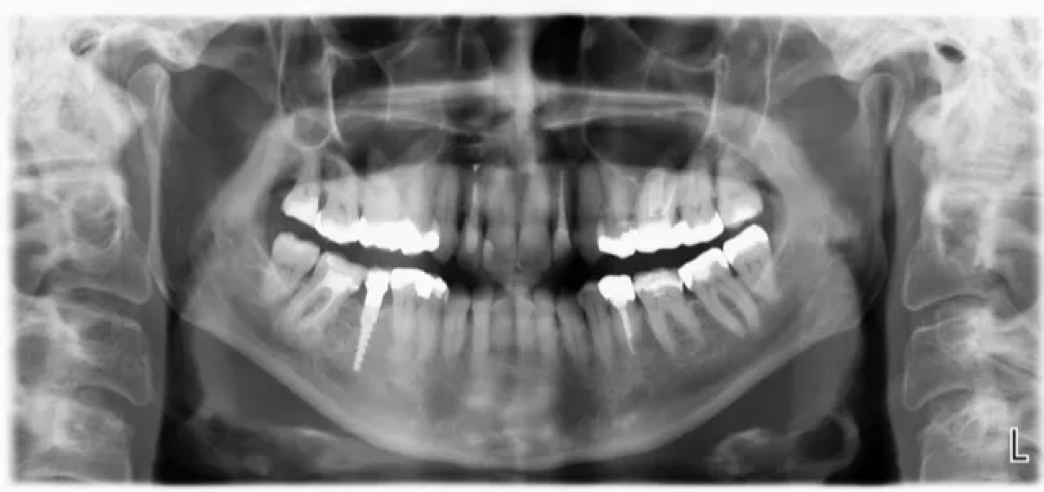

Strahungarmes Röntegen mittels digitalem OPG

Wir röntgen digital  = mit geringer Strahlenbelastung

x-ray mit geringer Strahlen-Belastung